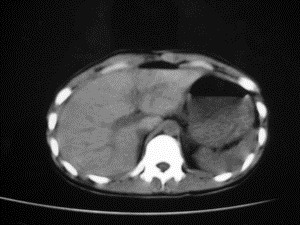

患者女,20岁,被车撞伤3小时,pe:全腹肌紧张,压痛反跳痛,以右上腹为著,肠鸣音减弱。有手术结果。![]() ![]() ![]() ![]() ![]() ![]() ![]() ![]() ![]() ![]() ![]() ![]() ![]() ![]() ![]() ![]() ![]() ![]() ![]() ![]() ![]() jiajie发言: ![]() 考虑空腔脏器穿孔。 dyqct发言:考虑:1、肝左叶外侧段断裂伤伴少量腹血。2、空腔脏器穿孔。 fangzheng发言:仅见腹腔内游离气体,提示空腔脏器穿孔。 guoke发言:胃内密度增高,肠腔内充满气体,考虑肠腔破裂出血 mmg94发言:胃后壁见一增厚软组织密度影,肝左叶前见游离气体影,左腹腔内局部肠管壁、系膜增厚。并见类圆形软组织。以上征象提示消化道管腔破裂,小肠、肠系膜挫裂伤,腹腔血肿形成。 拾荒者发言:肝实质密度不均匀,胃内见不均匀高密度影。考虑:肝挫裂伤,胃内应激性溃疡出血。 守望可可西里发言: 以下是引用jiajie在2006-6-20 15:49:00的发言:[br] [br][br]考虑空腔脏器穿孔。jiajie老师,我鼓起了很大的勇气才决定给您唱个反调儿,如果我错了,请您一定给我指出来,谢谢您了。我反复看了解剖图谱,觉得您所说的“考虑空腔脏器穿孔”上图所用箭头标明的不是游离气体。请您看以下几幅图片: ![]() ![]() ![]() ![]() ![]() ![]() ![]() ![]() 再请您看向医生老师发表的解剖图谱3幅 ![]() ![]() ![]() 这以下几幅图,我认为是肝包膜下积血。不过,说实在话,我没有发现有明显的肝挫裂伤。不对的地方请您一定指出来,再次感谢您了,jiajie 老师! ![]() ![]() ![]() ![]() 这下面几幅图片,我认为有明显的左中上腹部小肠损伤。 ![]() ![]() ![]() ![]() ![]() ![]() ![]() ![]() jiajie 老师,估计我说的是错误的,但我实在闹不明白,请您一定不要笑话我,并指出我的错误,以便于我减少工作中的失误。再次感谢您了,jiajie 老师! 至于胃内的不均匀高密度,我认为拾荒者战友说的有道理,胃内应激性溃疡出血和胃内容物混合所致。 手术结果:左肝叶(iv段)前缘长约8cm挫裂伤口,舌叶根部下< |